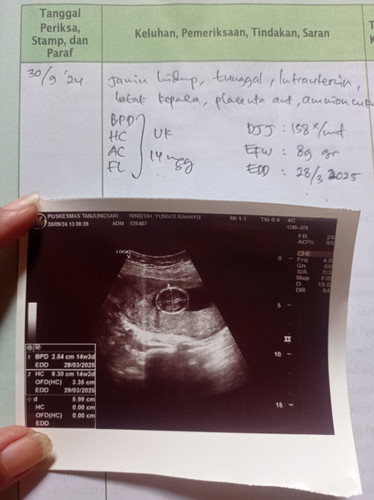

belum bund karna baru 14w3d bisa diliat jenis kelamin di 16w keatas ya bun tergantung posisi janin saat usg juga

Sepertinya belum keliatan itu bun, belum ada di catatan dokternya.

itu ada monas nya berati anak nya boy